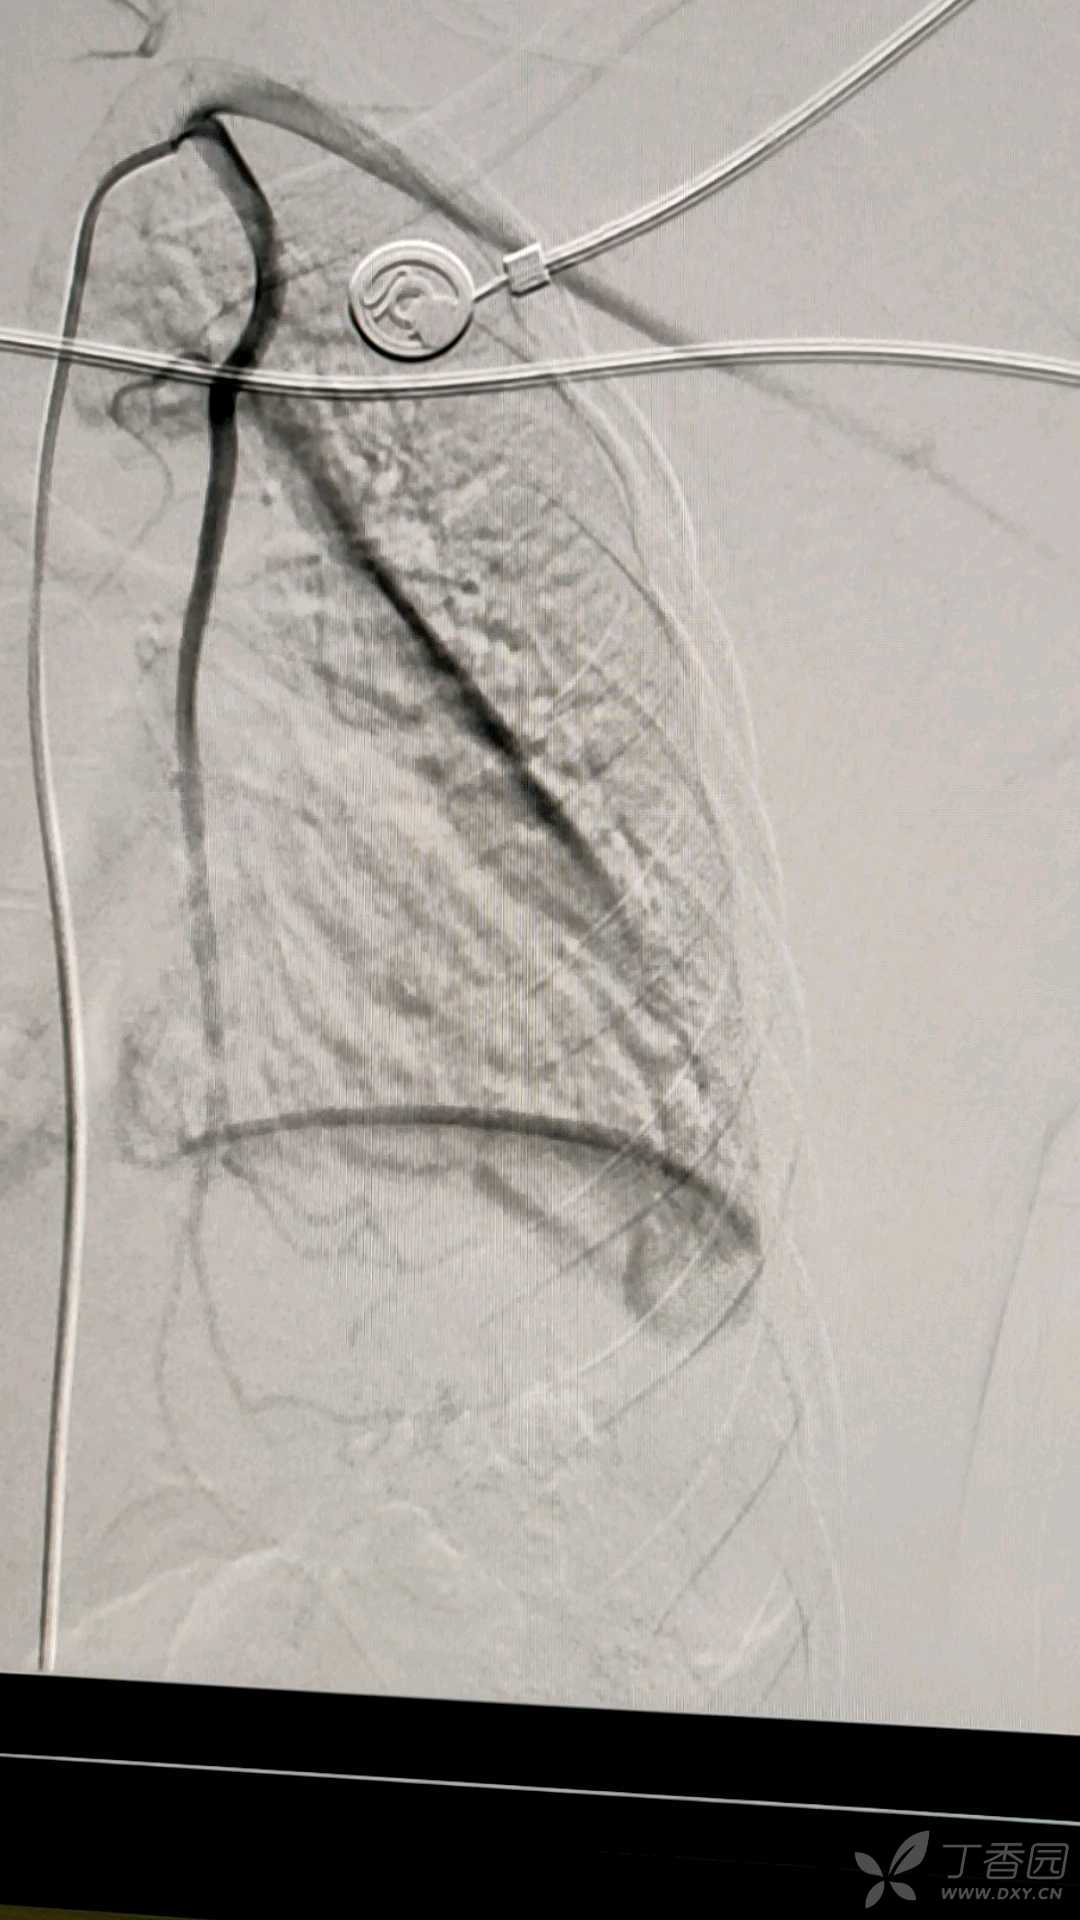

术中造影见下图

术中造影示,病灶主要由左侧胸廓内动脉分支供血,动脉期供血增粗,迂曲,实质期病灶明显染色。

术中使用平阳霉素4mg+1.5ml碘化油混合乳化液,PVA300栓塞治疗。再次造影显示病灶消失。如下图。